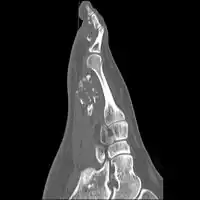

Medical imaging usually shows a well-defined wide-based bony growth on the surface of bone.[5] It can be pedunculated and irregular, giving it a "bizarre" appearance, and is not connected to underlying bone.[2]

X-ray left foot: Bizarre parosteal osteochondromatous proliferation in 2nd toe